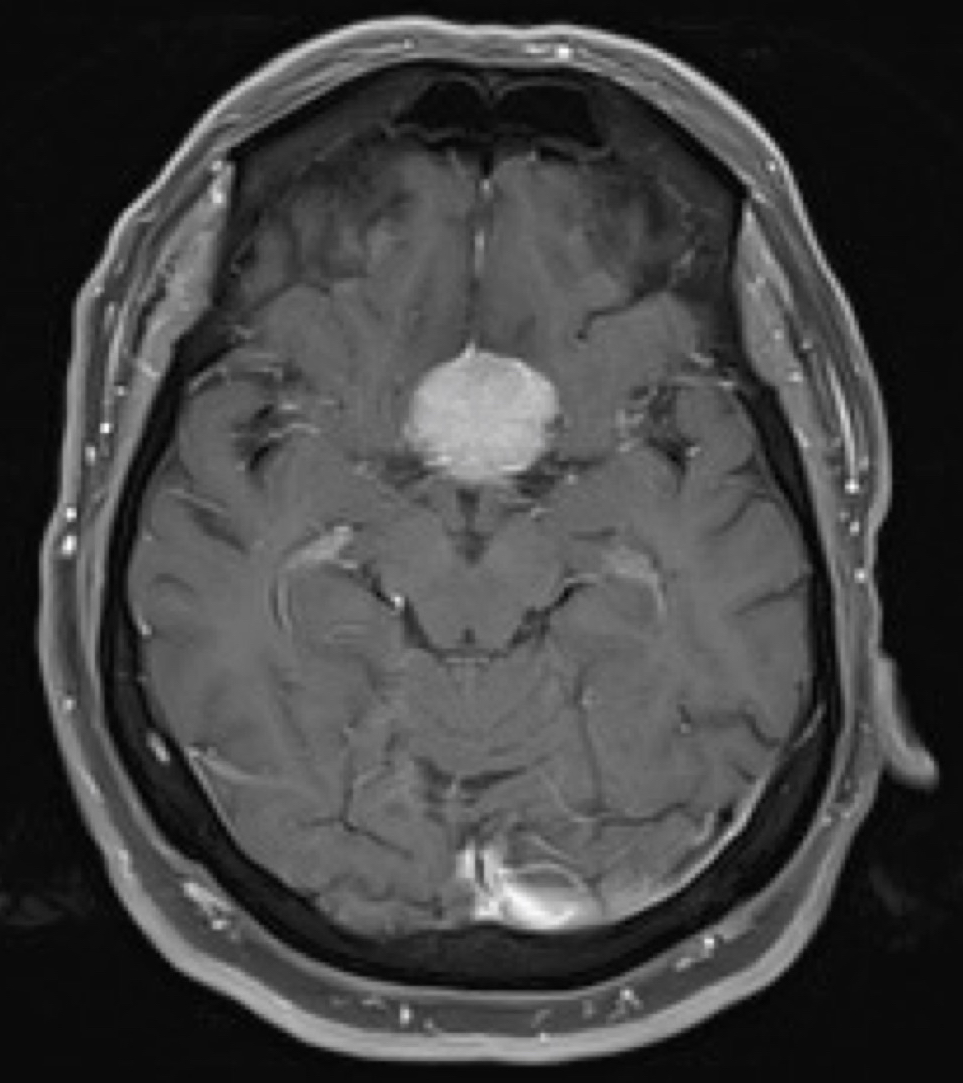

The tuberculum sellae (or the tubercle of the sella turcica) is a slight median elevation upon the superior aspect of the body of sphenoid bone (that forms the floor of the middle cranial fossa: 508-509 ) at the anterior boundary of the sella turcica (hypophyseal (pituitary) fossa): 509 and posterior boundary of the chiasmatic groove.: 509 A middle clinoid process flanks the tuberculum sellae on either side.: 509